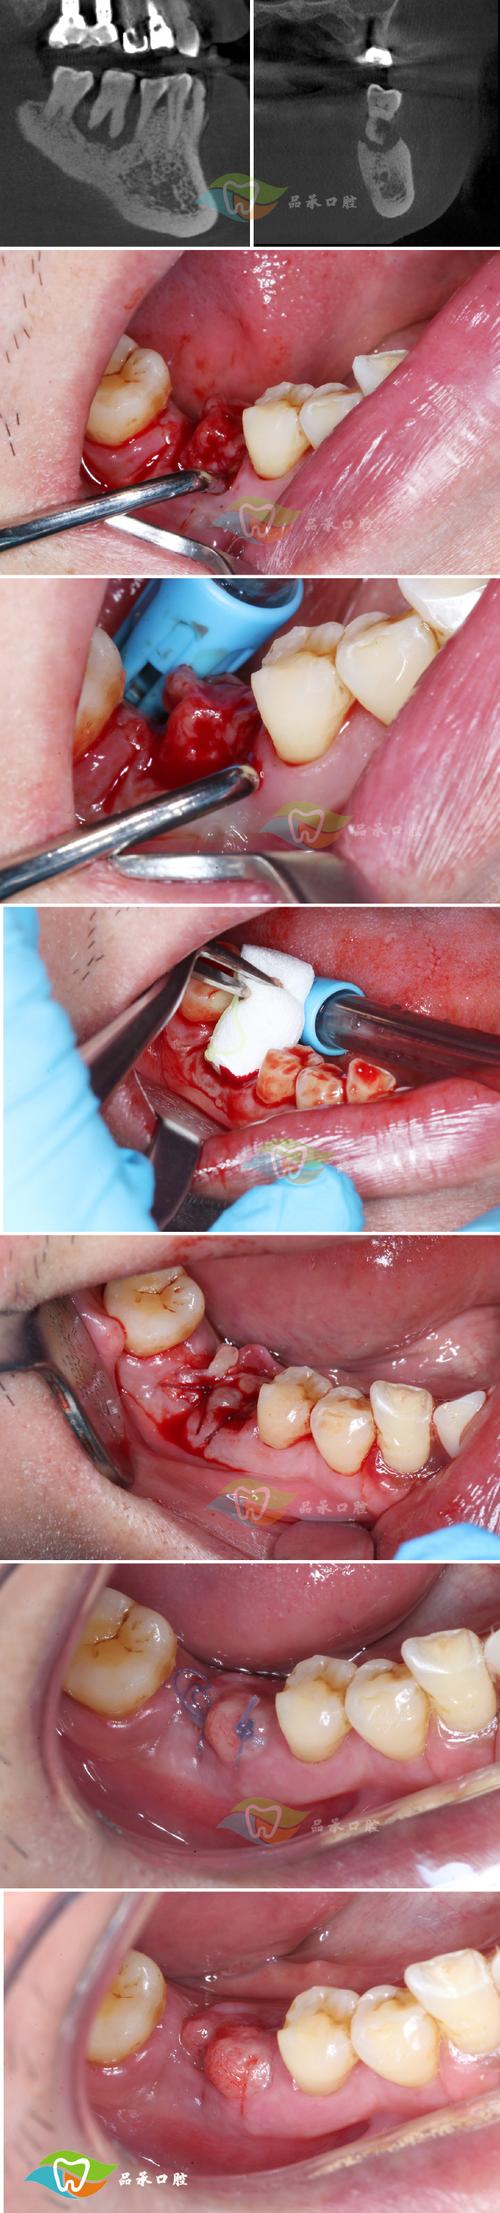

种植体周围组织愈合阶段的影响不可忽视,种植体植入后,需要与牙槽骨通过“骨结合”形成稳定连接,这一过程通常需要3-6个月,在此期间,种植体周围的牙龈、牙槽骨仍处于修复状态,咬合刺激可能引发组织水肿或轻微炎症,导致咬合感知异常,尤其是术后1个月内,咀嚼功能未完全恢复,咬合碰感可能更明显。

少数情况下,修复体本身的问题或术后并发症也会引发咬合异常,例如牙冠制作时密合度不足、边缘悬突,或种植体初期稳定性不佳,甚至术后感染导致局部组织肿胀,都可能影响咬合舒适度,若伴随疼痛、出血或牙冠松动,则需及时排查原因。

针对不同原因,医生会采取针对性处理:若为咬合高点,可通过精细调磨牙冠表面,去除早接触点,使咬合力分布均匀;若为种植体周围组织愈合期不适,可能需暂时调整咬合,避免患侧咀嚼,配合药物促进炎症消退;若修复体存在质量问题(如冠形态异常、边缘不密合),则需重新制作牙冠;若出现种植体松动或感染,则需评估是否需要进一步治疗,甚至重新种植。